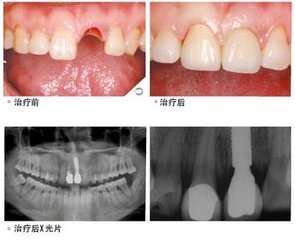

广州越秀圣贝口腔门诊部种植介绍,牙齿缺失时间久了,患者的牙槽骨会面临严重吸收风险,骨量也会出现不够的情况,而种植牙是要订到牙槽骨里,而且若本身存在一些口腔疾病, 但因缺牙而没及时处理,就很容易导致牙槽骨萎缩,因此会使治疗变得更加有难度。种植牙有哪些优点?

但长时间缺牙也是能做种植牙的,必须要先进行检查,看是否满足种植牙要求的口腔基础,才能做种植牙手术。

据科学调查显示,圣贝牙科拥有目前连锁对口腔牙列缺损、牙列缺失修复的较佳之一—种植。该是通过术前对患者牙槽骨进行数字化的影像扫描定位,并根据相关数据制作定位导向,而后“人工牙根”顺着定位导向植入牙槽骨,当“人工牙根”与牙槽骨生物相容稳固后即可进行镶牙.